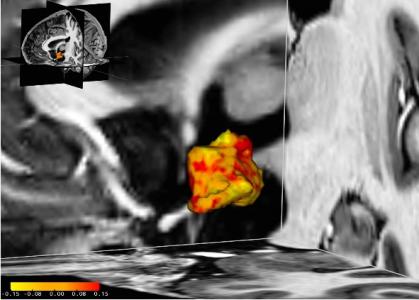

Chez ces patientes dépressives, les zones de l'hypothalamus (en rouge sur visuel) sont plus développées que chez leurs homologues en bonne santé. Les chercheurs suggèrent que cette « hypertrophie » pouvait résulter soit d’une prédisposition, soit de l’exposition à des facteurs de stress environnementaux. On savait déjà sait que les personnes plus prédisposées à la dépression présentent un dérèglement du système de réponse au stress endogène ou axe hypothalamo-hypophyso-surrénalien (axe HPA), qui est normalement déclenché en cas de situation stressante. Cette réponse augmente les niveaux de cortisol, fournissant au corps plus d'énergie lorsqu'il est confronté à une menace ou à un défi. Une fois la situation difficile passée, plusieurs mécanismes de contrôle de l'axe HPA garantissent normalement un retour à l'équilibre du système.

Un dysfonctionnement du mécanisme de rétroaction de l’axe HPA : chez les personnes souffrant d'un trouble dépressif ou prédisposées à la dépression, ce n'est pas le cas. Le dysfonctionnement du mécanisme de rétroaction entraîne une réponse au stress fonctionnant à plein régime, même en l'absence de stress apparent. Jusqu'à présent, la raison sous-jacente de ce système de réponse au stress hyperactif et le rôle de l'hypothalamus dans ce processus restaient mal connus. L’étude menée à l'aide d'un scanner IRM haute résolution auprès de 84 participants, révèle que :

- l'hypothalamus gauche est en moyenne de 5% supérieur chez les patients dépressifs vs leurs homologues en bonne santé ;

- cette constatation est effectuée également chez des patients souffrant de trouble bipolaire ;

- enfin, chez un groupe de participants souffrant de dépression, plus la dépression est sévère, plus l'hypothalamus est élargi ;

- enfin, les traitements antidépresseurs n'ont eu aucun effet sur la taille de l'hypothalamus.

Bien que de précédentes études aient montré que cette structure cérébrale est plus active chez les personnes souffrant de dépression ou de trouble bipolaire, on ne sait pas encore quel rôle joue cet hypothalamus plus important.

Les chercheurs suggèrent ici que son activité plus élevée chez ces patients pourrait mécaniquement entraîner des changements structurels et donc un volume plus important. Quoiqu’il en soit c’est un marqueur intéressant, pour la détection, de la dépression.